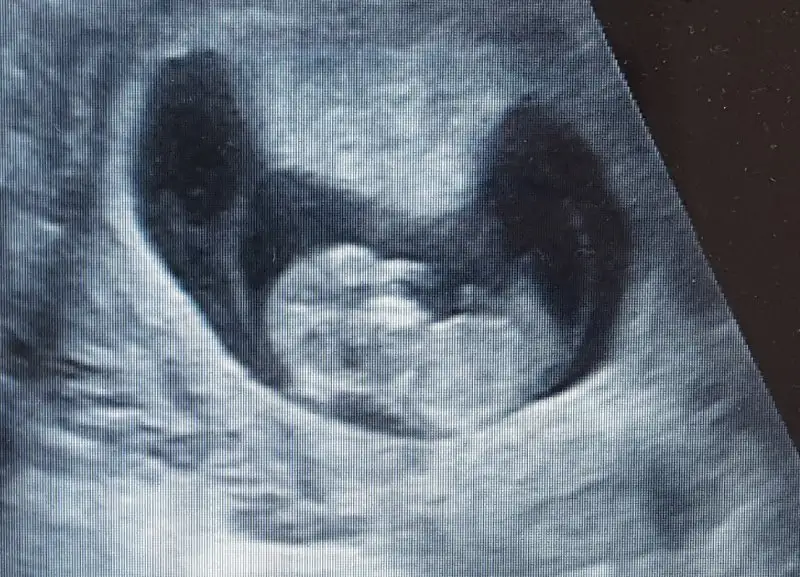

Anlayanlar bize de el atin kiz mi erkek mi. Birisi kiz birisi erkek dedi simdiye kadarEki Görüntüle 2093137

Bas ve gövde değil mi gözüken. Orda sanki kordon da gördüm ben. Belden aşağısınını göremedim. Yandan profil gibi geldi bana resim. Bırdan kız erkek demek cok zor. Bacak arası resmi lazkm veya nub tahmını icin yandan belden aşağısı lazım fotik